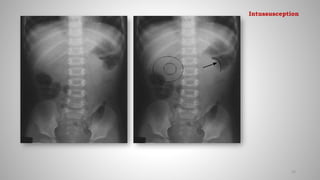

Imaging features:

Plain X-ray(Abd)

• Plain radiograph is normal in 25%.

• Small tissue mass and crescent of air around the intussuceptum in the

right abdomen.

• Small bowel obstruction

• Paucity of bowel gas distally

• Meniscus sign: Crescent of gas within colonic lumen that outlines the

apex of intussusceptum